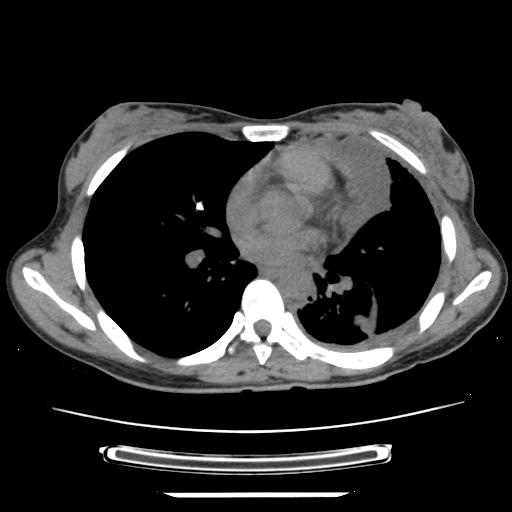

女,29岁,胸部不适,在外院胸片提示胸腔积液,到我院ct检查。

纵膈窗

左肺上叶不张,左侧胸水,叶间裂积液,纵隔淋巴结,脾脏钙化,考虑左肺上叶支气管内膜结核,结核性胸膜炎,脾结核

支持两肺继发性肺结核,左侧胸膜腔包裹性积液、胸膜肥厚,脾内多发钙化(结核钙化)。

支持 两肺继发性肺结核,左侧胸膜腔包裹性积液、胸膜肥厚;脾内多发钙化(结核钙化)。

两肺继发性肺结核,左侧胸膜腔包裹性积液、胸膜肥厚;脾内多发钙化(结核钙化)。支持!